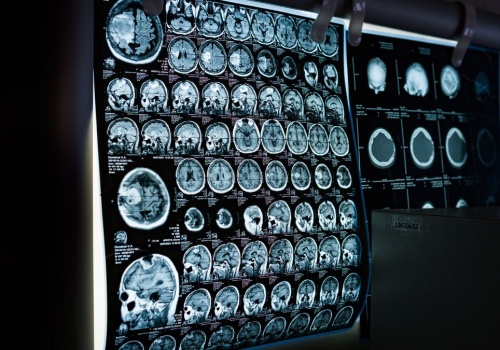

Zamrożony mózg, który znów działa? Naukowcy z Niemiec dokonali przełomu, przywracając aktywność w tkance mózgowej po ekstremalnym schłodzeniu. To odkrycie może otworzyć zupełnie nowe możliwości w medycynie i ratowaniu życia. Przez lata krioprezerwacja była kojarzona głównie z filmami science fiction...